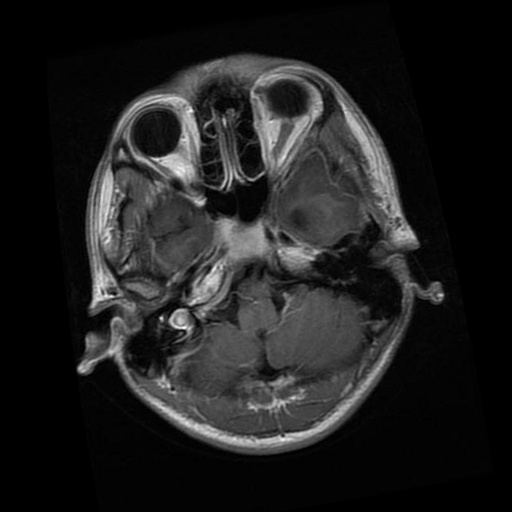

We use the public Brain MRI dataset from Kaggle111https://www.kaggle.com/datasets/masoudnickparvar/brain-tumor-mri-dataset, a widely adopted in the literature for brain-tumor classification. The dataset consists of 2D axial brain MRI slices, provided as raster images with variable spatial resolutions and aspect ratios.

The images were labeled into four categories: no tumor, glioma, meningioma, and pituitary. In the original release, the class counts are no tumor (2000), glioma (1621), meningioma (1645), and pituitary (1757), totaling 7023 images. Table 2 presents the distribution of instances per class along with representative visual examples.

| Class | Quantity | Example |

|---|---|---|

| No Tumor | 2000 | ![]() |

| Glioma | 1621 | ![]() |

| Meningioma | 1645 | ![]() |

| Pituitary | 1757 | ![]() |

| Total | 7023 |